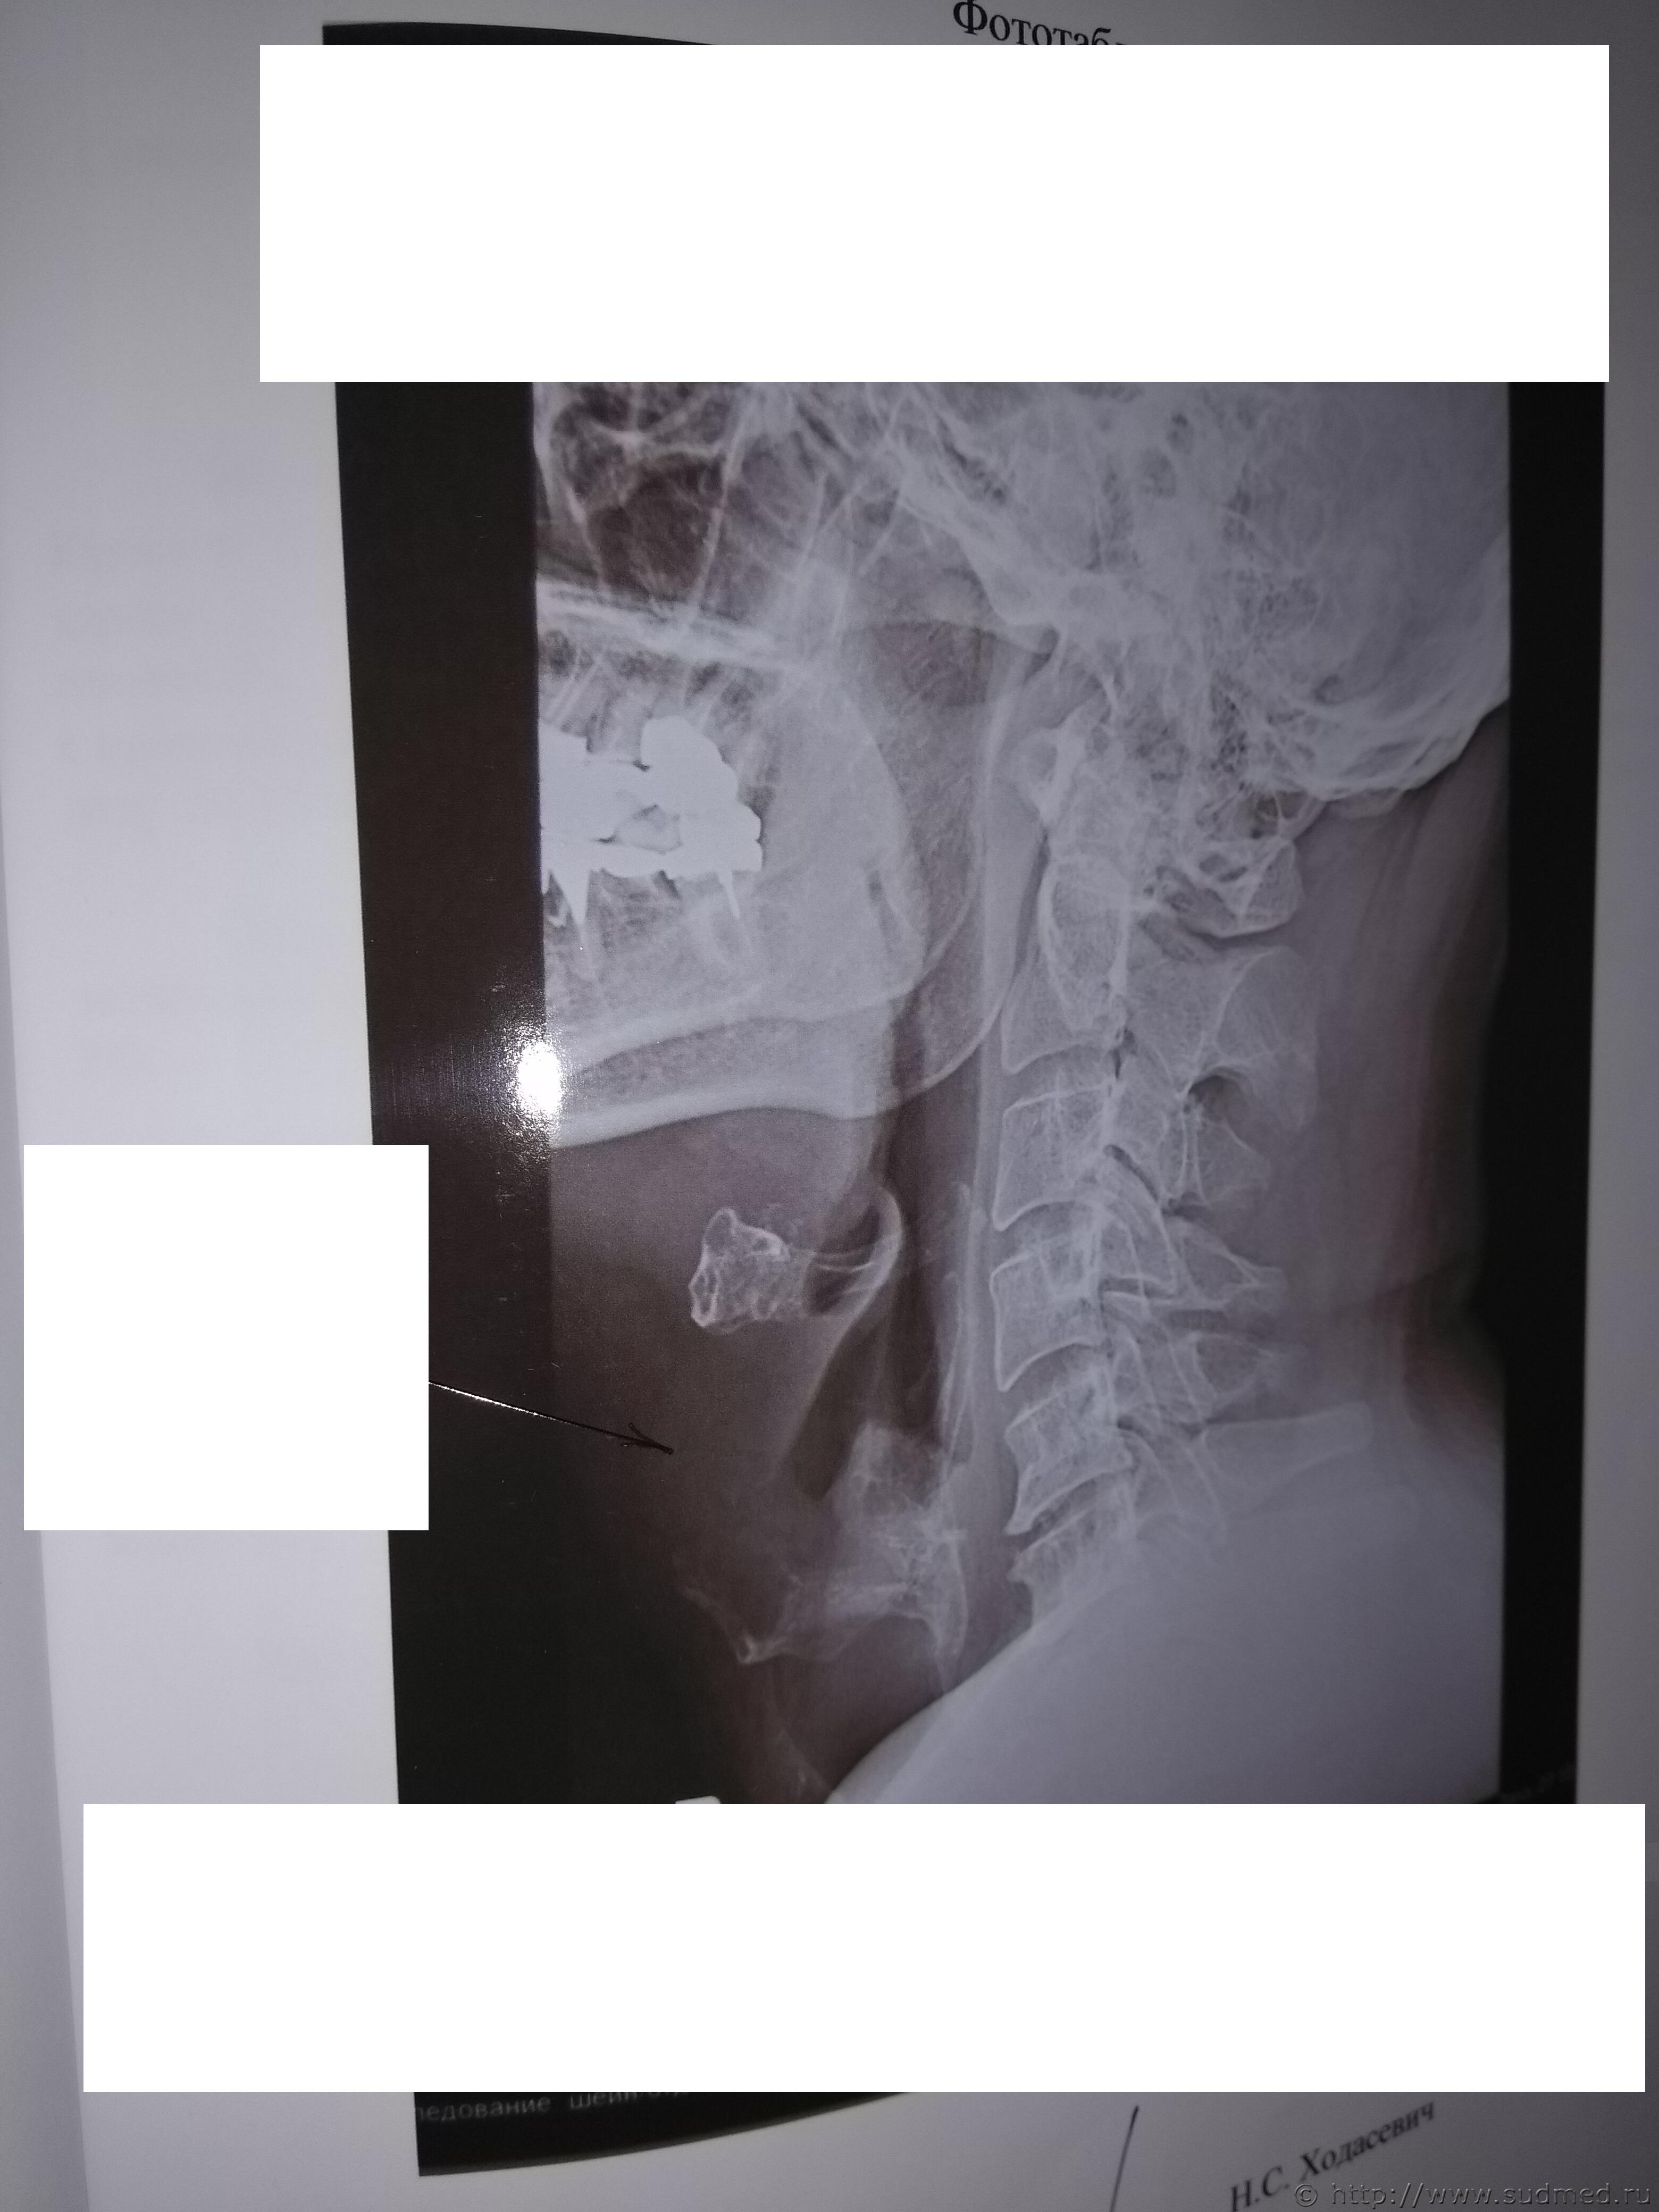

Какие повреждения видны на этой фототаблице?

Похоже на перелом щитовидного хряща, но утверждать не берусь: качество изображений низкое.

А мне кажется там компрессионный 5-6-го, либо перенесенный в анамнезе.

Между тем врач рентгенолог на суде сказал:

1. Снимок сделан для исследования костных структур шеи. Объясняется тем, что в центре снимка находится позвоночник, а не гортань. У рентгеновского аппарата два режима, один для исследования костных структур, второй для исследования мягких тканей.

2. На рентгеновском снимке не видно щитовидного хряща. Т.е. получается как в одном фильме. Ты суслика видишь. Нет. А он здесь есть.